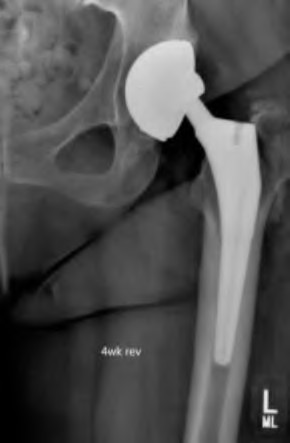

An 82-year-old woman falls and sustains the fracture shown in figure A. She denies any history of dislocation or prodromal pain prior to her fall. What is the most appropriate treatment?

The radiograph demonstrates a periprosthetic femur fracture extending to the tip of the stem. The long spiral fracture is consistent with a loose implant. The bone stock is sufficient. Therefore, this fracture pattern would classify as a B2 using the Vancouver classification system. The Vancouver classification for periprosthetic femoral fractures is simple yet incorporates all the pertinent factors such a location, stem fixation, and bone stock. Type A is a trochanteric fracture- lesser or greater. These can be treated non-operatively usually and ORIF if symptomatic. Type B fractures are around or just below the stem and are subdivided into three types. Type B1 is a fracture with a well fixed stem.

The treatment is cable plating or allograft struts or a combination of the two. Type B2 is a fracture with a loose stem with good bone stock. The treatment is a cementless porous coated long stem atleast two diameter length past the

fracture site. Type B3 is a fracture with a loose stem and comminution. For younger patients, use cementless porous coated long stems with allograft struts. For older patients, consider a tumor prosthesis. Cement fixation is sometimes necessary Type C is a fracture well below the stem tip. These can be treated independently of the prosthesis.

Springer et al showed optimal outcomes with revision involving long extensively-coated femoral stems for Vancouver B fractures.

Masri et al review the classification and treatment of periprosthetic femur fractures.